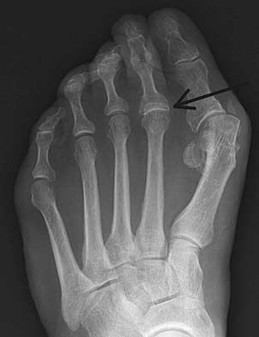

Figures 9a and 9b are the radiographs of a 19-year-old woman with a painful juvenile bunion. The pathologic findings associated with this deformity

include a

The radiographs show a hallux valgus deformity with a laterally deviated distal metatarsal articular surface, a large intermetatarsal angle with medial deviation at the first metatarsocuneiform joint, an elongated medial collateral ligament, and a contracted lateral collateral ligament. There is no distal 1-2 transverse intermetatarsal ligament. The distal transverse ligament in the first interspace extends from the second metatarsal to the lateral (fibular) sesamoid, remains intact, and keeps the sesamoids in a lateral position as the first metatarsal head migrates medially.